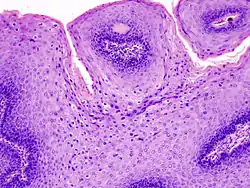

Micrograph of a genital wart with the characteristic changes (parakeratosis, koilocytes, papillomatosis). H&E stain.

The diagnosis of genital warts is most often made visually, but may require confirmation by biopsy in some cases.[21] Smaller warts may occasionally be confused with molluscum contagiosum.[20] Genital warts, histopathologically, characteristically rise above the skin surface due to enlargement of the dermal papillae, have parakeratosis and the characteristic nuclear changes typical of HPV infections (nuclear enlargement with perinuclear clearing). DNA tests are available for diagnosis of high-risk HPV infections. Because genital warts are caused by low-risk HPV types, DNA tests cannot be used for diagnosis of genital warts or other low-risk HPV infections.[4]